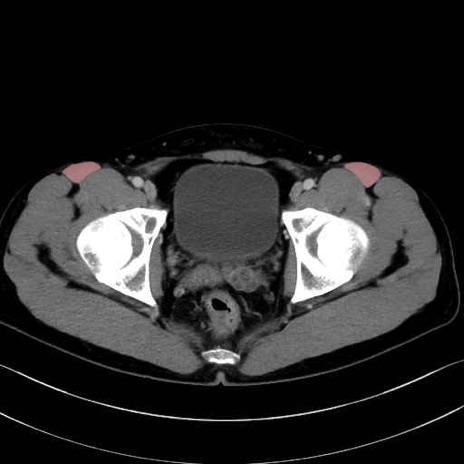

縫工筋 (Sartorius)